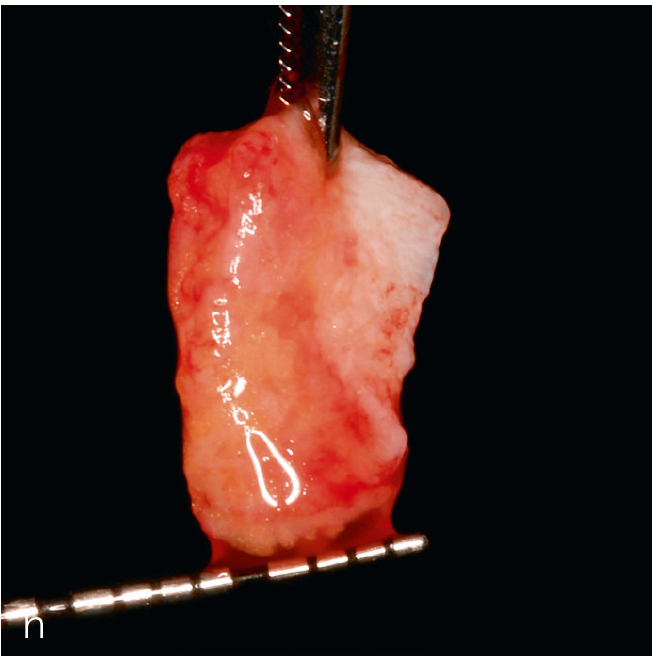

Die kombinierte chirurgische Periimplantitstherapie ist bei fortgeschrittenen Knochendefekten mit komplexer Morphologie indiziert64 (Abb. 3). Die Kombination augmentativer Verfahren mit der Implantoplastik, die am suprakrestalen Implantatanteil vorgenommen wird, zeigt nach einem Beobachtungszeitraum von 7 Jahren eine hohe Effektivität48,65.

Abb. 3a bis h Falldokumentation mit Zustand nach Implantation und lateraler Augmentation alio loco: a) klinische Ausgangssituation mit Fistelung vestibulär in der Region 12; b) klinische Parameter (PI=Plaque Index 1-3, ST=Sondierungstiefe, MR=Mukosarezession, KM=keratinisierte Mukosa, BOP=Bleeding on probing, SUPP=Suppuration); c) radiologische Ausgangssituation mit initialem periimplantären Knochenabbau; d) operativer Zugang; e) Defektdarstellung nach Entfernung des periimplantären Entzündungsgewebes; f) Defektaugmentation mit einem Gemisch aus Eigenknochen und xenogenem Knochenersatzmaterial; g) Kollagenmembran; h) das aus dem Gaumenbereich entnommene Bindegewebstransplantat (BGT).